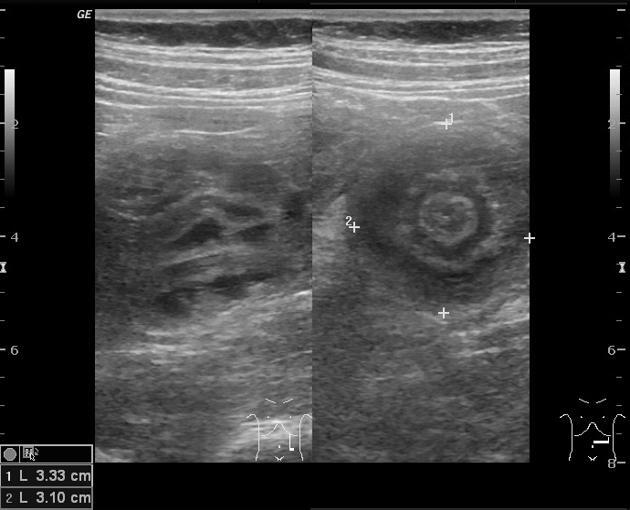

What is the key diagnostic test for bowel intussusception?

A

Target sign - concentric echogenic and hypoechogenic bands on ultrasound.

May also show complications such as free abdominal air or the presence of gangrene.